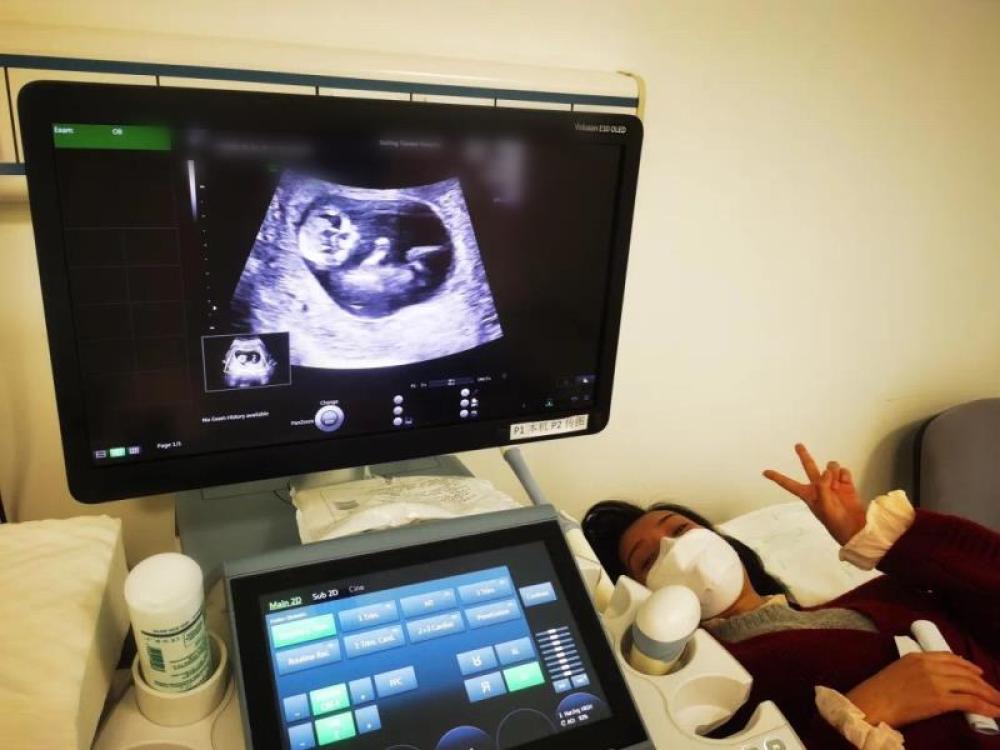

今天是我来武汉的第54天,第一次通过B超影像见到了“小家伙”。

今天一早,妻子去医院进行B超检查,同事用手机拍摄下了B超显示屏上的画面,记录下了这个87天的小家伙第一次“亮相”。

图为北京天坛医院袁磊爱人做B超检查。

“袁磊,看看你们家宝宝,可爱吗?”收到同事发来的视频,第一眼就看哭了,身边的同事看完视频也哭了。

视频里,这个小家伙好像听到了外面的召唤,在妈妈的肚子里伸手、踢腿、翻身,用各种动作进行回应……看到他那小胳膊小腿,一种从未有过的幸福感不停地向上涌,眼泪怎么也控制不住。

其实在武汉这么多天,他一直就是我的牵挂,今天终于看到他了,那种感受真是又紧张又激动,虽然还看不清他的样子,但是已经感受到他的活力。

我想,如果是儿子的话,小名就叫“袁保”,保卫的保;如果是女儿,小名就叫“袁援”,支援的援。